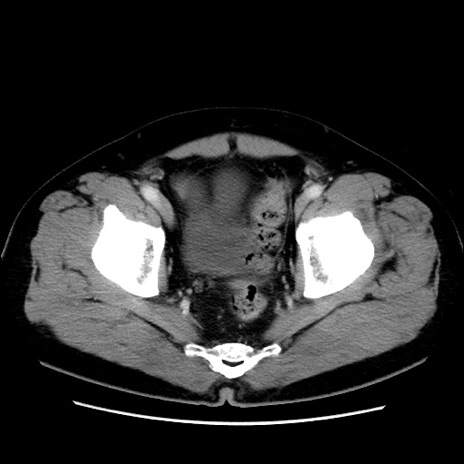

症例16(横断像)

【症例】 70歳代男性

【主訴】 腹痛、嘔吐

【現病歴】 約1ヶ月前より間欠的に腹痛と嘔吐あり、当院消化器内科を受診したところCTで多発する肝臓のLDAを指摘され、精査中であった。以降は消化器症状は安定していたが、2日前より嘔気と腹痛があり、同日より排便・排ガスが消失した。改善認めず、 本日、救急外来を受診した。

【既往歴】 大腸ポリープ切除後。

【身体所見】意識清明・会話良好、BT 36.3℃、BP 127/80mmHg、 P 80bpm、腹部:膨満あり、平坦・軟、上腹部正中および下腹部正中に圧痛あり、反跳痛なし、筋性防御なし。

【データ】WBC 7200、CRP 0.77